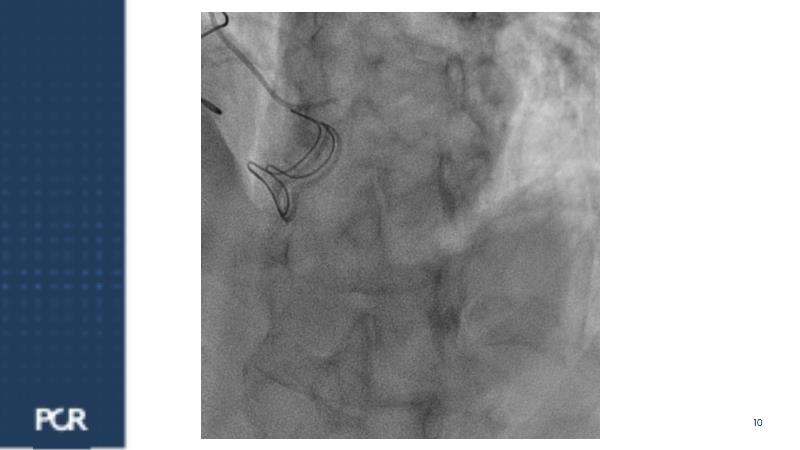

Watch this session focused on a patient with distal left main stenosis to understand that the stepwise provisional side branch (SB) stenting strategy is the standard approach for most left main trifurcation lesions. Discover the importance of optical frequency domain imaging for strategy determination and bifurcation PCI outcome optimization. Learn about the Ultimaster Nagomi™ DES, inheriting features from the Ultimaster Tansei™ stent, tailored for complex bifurcation anatomy with enhanced deliverability and overexpansion capacity.